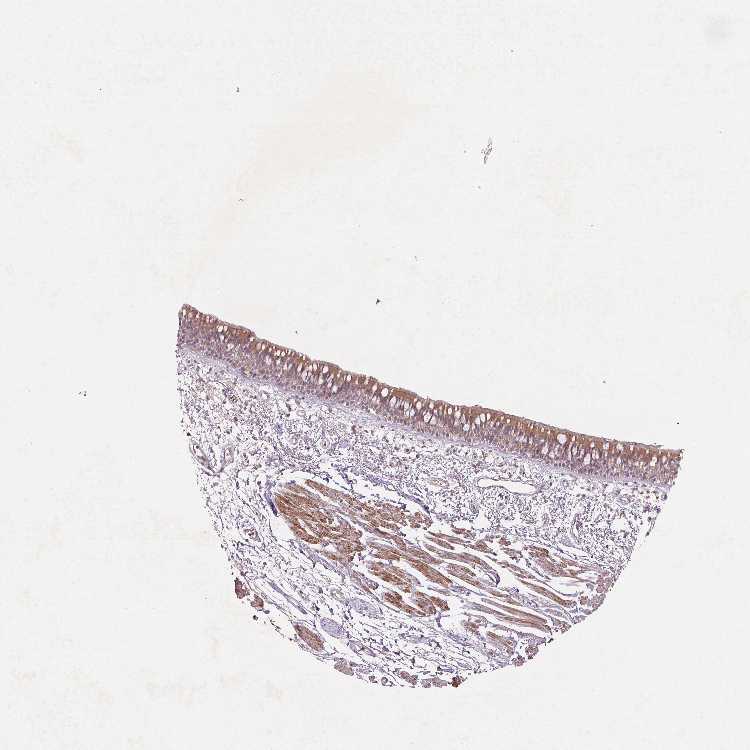

Antibody HPA064861

Respiratory epithelial cells Medium